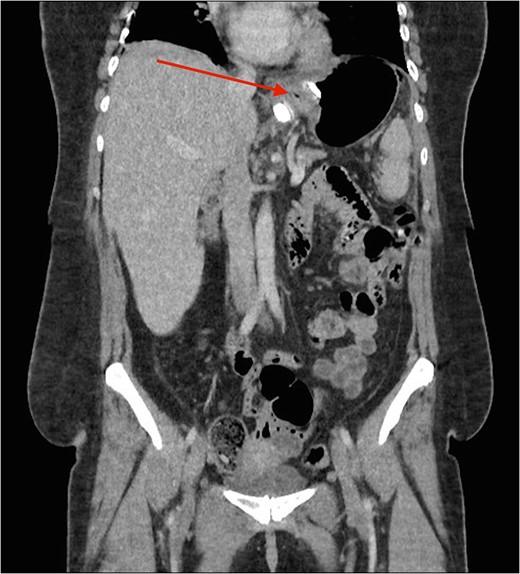

Cross section CT image demonstration the site of the band with no collection (red arrow).